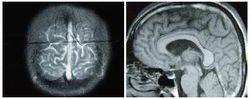

腦靜脈竇血栓形成(cerebral venous sinus thrombosis,CVST)是一種特殊類型的腦血管疾病,發生率不足所有卒中的1%。通常以兒童和青壯年多見,而兒童患者中又以感染引起的側竇和海綿竇多見。化膿性中耳炎和乳突炎患者易並發橫竇(transverse portion of lateral sinus)和乙狀竇(sigmoid portion of lateral sinus)的血栓形成,統稱為側竇血栓形成(lateral sinus thrombosis)。根據病變性質,CVST可分為炎症型和非炎症型兩類。炎症型中海綿竇和橫竇是最常受累的部位。而非炎症型中上矢狀竇最容易受累。橫竇乙狀竇血栓形成多繼發於化膿性乳突炎或中耳炎。

腦靜脈竇血栓形成為了更好地理解CVST的臨床症狀和體徵,首先應該區分兩種不同的病理生理機制。即腦靜脈血栓——由靜脈梗阻所產生的局灶性症狀;腦靜脈竇血栓——由靜脈竇血栓導致顱內高壓。在大多數患者中,這兩種病理生理過程常同時存在。腦靜脈的閉塞產生局部腦水腫和靜脈型梗死。病理檢查可發現擴大、腫脹的靜脈,水腫(包括細胞毒性水腫和血管源性水腫),缺血性神經元損害和點狀出血。而後者可融合成大的血腫被CT檢測到。橫竇乙狀竇血栓形成可導致靜脈壓升高,從而影響了腦脊液的吸收而產生顱內高壓。因為影響的是腦脊液循環的最後通路,蛛網膜下腔和腦室之間沒有壓力梯度,所以腦室並不擴張,也不會導致所有的患者都出現腦積水。